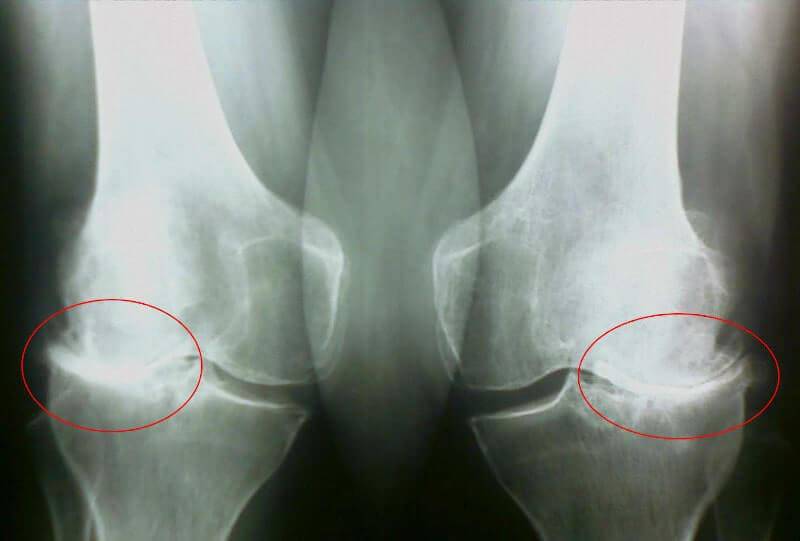

Как ни верти, а пришлось идти к врачу, жена моя настояла на этом. Терапевт отправил меня к ревматологу, попасть к которому мне удалось через месяц с лишним, очередь, однако, не один я суставами маюсь, нас таких оказалось много. Встретила меня ну очень пожилая врач, ничего не говоря отправила меня на рентген и анализы крови/мочи. На втором приеме за пару минут поставила мне диагноз — какой-то артроз, первичный или вторичный, сейчас уж точно не помню, да и не важно это.

35 день: сдал анализы и сделал рентген. Никаких следов артроза! Хрящи в суставах как у 30-ти летнего пацана. Докторша сказала, что на предыдущем рентгене скорее всего был дефект, поэтому диагноз артроз был ошибочным.